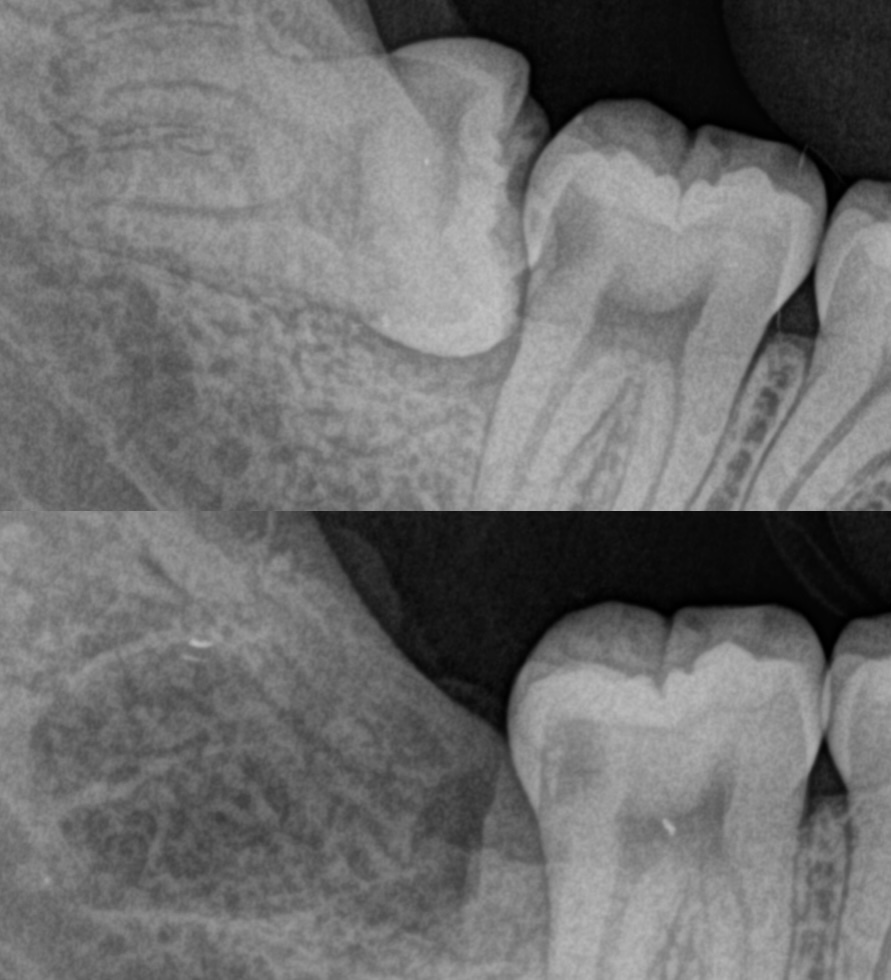

一般歯科

歯が不自由になると何より「食」を満足に楽しめなくなり、引いては全身の健康を損ねる原因となりかねません。つまり常に歯を健やかに保っておくことこそが、いつまでも元気でいられる秘訣であると言えます。おいしいものを当たり前のようにおいしく食べられること、それが充実した食生活。その実現のために、私たちは歯の治療はもちろんのこと、日常の手入れや予防策などを的確にアドバイスしていくことも大切な使命と考えています。

当院は家庭的な雰囲気を持ったクリニックです。患者さんに負担をかけず最小限の治療・自分の歯を大事にする治療を心がけています。ご相談・ご要望がございましたら、お気軽にご来院ください。